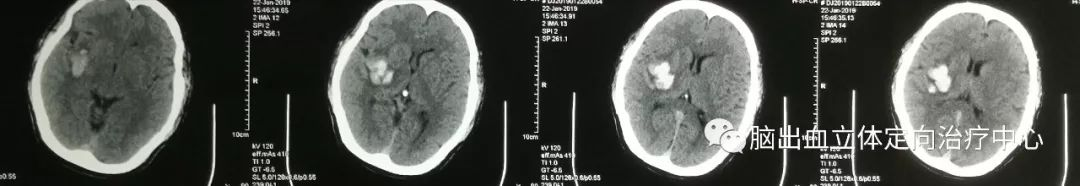

入院时CT:

患者意识呈嗜睡状,呼之能应,能正确回答问题,遵嘱动作,给予非手术治疗,一天后患者意识加重至朦胧,诉头痛明显,左侧面部发汗异常,双侧瞳孔左=右,直径约2mm,对光反射可。

复查CT示:侧脑室、三脑室较前受压明显,血肿周围分层低密度明显

仔细观察CT片可见血肿呈分层现象

再仔细观察并划定血肿分层区域,可设定血肿为高密度区域、低密度区域,和正常脑组织对比

以红色区域划分为高密度区域、蓝色区域划分为低密度区域

测量各密度区域CT阈值,可见高密度区域(红色区域)CT阈值为60.66,低密度区域(蓝色区域)CT阈值为44.39,正常脑组织区域CT阈值为20.94。